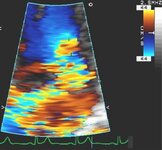

Corte apical de 4 câmaras de regurgitação mitral 4+ (grave) e uma grande área de superfície de isovelocidade proximal

Do acervo de Samir Kapadia e Mehdi H. Shishehbor